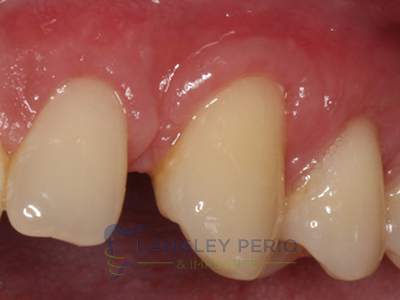

Case 2

Connective tissue grafting was done to cover exposed root surfaces to help to prevent root cavities from developing and reduce temperature sensitivity.